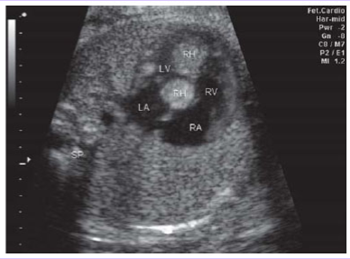

Rhabdomyoma

Benign tumor of striated muscle.

Most common primary cardiac tumor in children.

Multiple in 90% of cases, but can be isolated.

Most frequently arise in the ventricular myocardium.

<p>Benign tumor of striated muscle.</p><p>Most common primary cardiac tumor in children.</p><p>Multiple in 90% of cases, but can be isolated.</p><p>Most frequently arise in the ventricular myocardium.</p>

1. Well-circumscribed, homogenous, hyperechoic mass

2. Small, multiple lesions - may appear as thickened myocardium

Sonographic appearance of rhabdomyomas (2).

<p>Sonographic appearance of rhabdomyomas (2).</p>